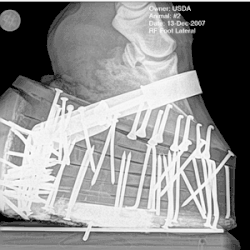

Soring can be detected by observing the horse for lameness, assessing its stance and palpating the lower legs. Some trainers trick inspectors by training horses not to react to the pain that palpation may cause, often by severely punishing the horse for flinching when the sored area is touched. The practice is sometimes called "stewarding", in reference to the horse show steward. Some trainers use topical anesthetics, which are timed to wear off before the horse goes into the show ring. Pressure shoeing is also used, eliminating use of chemicals altogether. Trainers who sore their horses have been observed leaving the show grounds when they find that the more stringent federal inspection teams are present.[35]